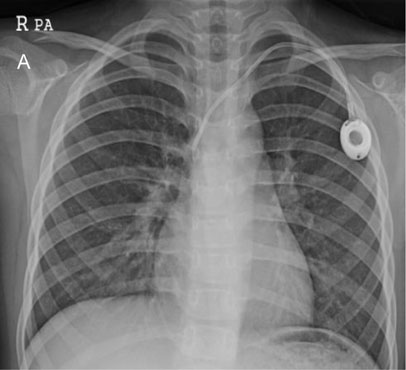

Fig. 2-A

TIVD inserted through left IJV before a removal operation.

Fig. 2-A TIVD inserted through left IJV before a removal operation.